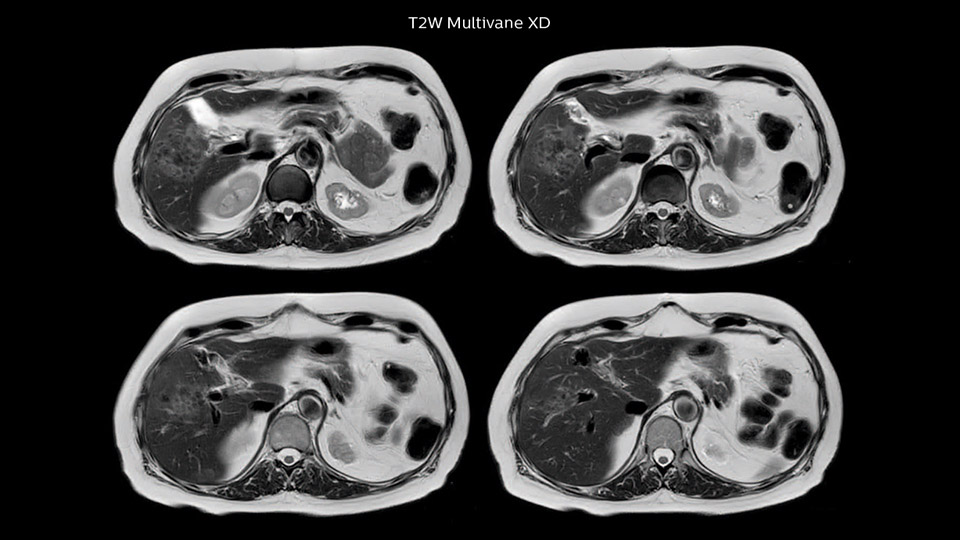

Comparison of liver MRI with and without MultiVane XD motion correction

In this example the image quality of the MultiVane XD images is evidently better than in the images without MultiVane XD. Ingenia 1.5T with dS Torso coil solution.

“We acquire one transversal high resolution T2-weighted sequence with 3 mm slice thickness, for example for pancreas or liver lesions. Then we also add a T2 fat suppressed MultiVane XD SPIR sequence. We perform these two routinely in our liver imaging. We use high dS SENSE factors to significantly shorten scan times to 2-4 minutes, which can improve our protocol; it’s a very robust scan.”